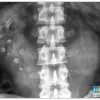

IV. Chẩn đoán x-quang

– Trong trường hợp điển hình thấy hình ảnh bóng 2 thận xoay trục với cực dưới hướng vào trong phía cột sống, gần nhau, cực trên xa nhau.

=> Case lâm sàng 1: